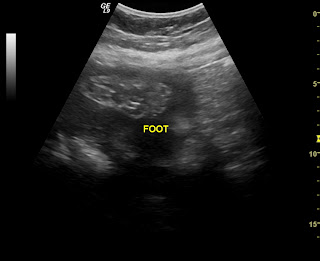

Only 9 weeks to go! I can't believe it is down to only two months, where did the time go? Well, we just had another ultra sound done. You can check out all her wonderful pics. They figure she weighs about 4 lbs 1oz. I think she has the biggest cheeks ever, and I think she has my nose. She is doing fine and is actually big for her "age". She is always moving and kicking. And she seems to have the hiccups a lot.

I know it has been awhile since I have updated this. Sorry about that. Everything is going pretty well. I had my 20 week ultra sound done about 2 weeks ago. I found out it's a girl! They couldn't see her very well so I had another ultra sound done again today. She looks absolutely beautiful. They did find a problem though. She looks fine, but there is a problem with the umbillical cord. A normal one has 3 vessals, 2 veins and 1 artery. The problem with mine is that it only has 2 vessals. One vein and one artery. I haven't done the research yet so I am not positive the effects this can have on her. The doctor said it is something they have to watch so I am going to have an ultrasound done once a month to make sure she is still growing and developing appropriately. Right now she looks good, she weighs 1lb 2oz. I will post more information as I get it. For now I am going to post all of her ultra sound pictures starting with her super early ones. So enjoy and know that I have only 4 mos to go!